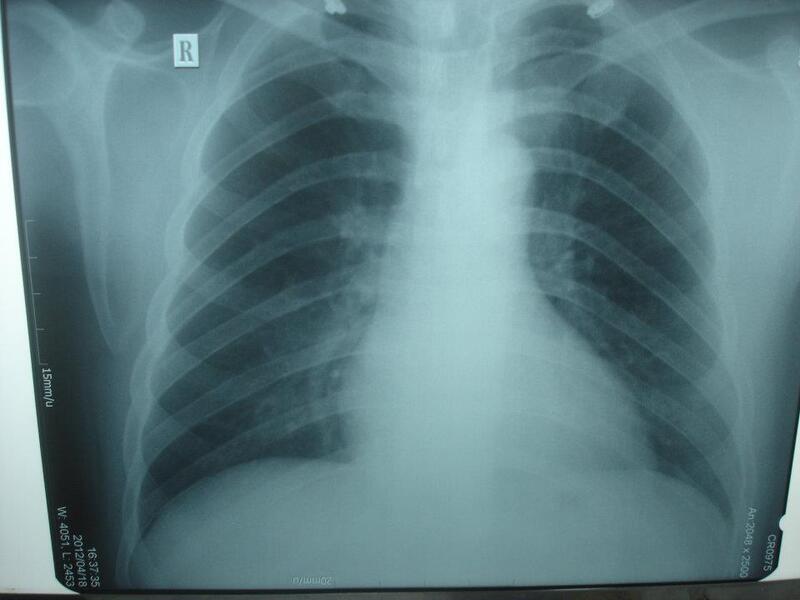

3. Xét nghiệm chẩn đoán viêm phổi bằng hình ảnh X quang lồng ngực

Khi bệnh cảnh lâm sàng nghi ngờ viêm phổi, bệnh nhân cần được chụp X quang lồng ngực. Triệu chứng “đám mờ” trên X quang lồng ngực được xem là “tiêu chuẩn vàng” cho chẩn đoán viêm phổi.

Tuy nhiên cần lưu ý hai tình huống sau đây:

Có “đám mờ” nhưng không phải viêm phổi (dương giả) gặp trong các trường hợp: Viêm phổi do các bệnh lý khác không nhiễm trùng (viêm mạch máu, phản ứng thuốc); bệnh phổi mô kẽ; phù phổi trong suy tim ứ huyết, hẹp hai lá; nhồi máu phổi; xuất huyết phế nang; xẹp phổi; ung thư phế quản.

Không có “đám mờ” nhưng vẫn là viêm phổi (âm giả) gặp trong các trường hợp: Mất nước; giảm bạch cầu đa nhân trung tính; bệnh diễn tiến vào giai đoạn sớm, chưa kịp xuất hiện triệu chứng X quang; viêm phổi do P. carinii trên bệnh nhân suy giảm miễn dịch (AIDS).

- X quang lồng ngực cho thấy viêm phổi xấu đi nhanh được định nghĩa là tổn thương mờ ở phế trường tăng thêm 50% sau 36 giờ.

- Triệu chứng cận lâm sàng: Triệu chứng huyết học như giảm bạch cầu < 3000/mm3 hoặc tăng > 30.000/mm3; Hemoglobin máu < 0,9 g%. Triệu chứng sinh hoá máu như creatinin máu > 1,5 mg% hoặc BUN > 20 mg%; PaO2 < 60 mmHg hoặc PaCO2 > 48 mmHg với oxy khí trời; Albumin máu < 30 g/lít. Triệu chứng vi sinh học bao gồm viêm phổi do P. aeruginosae hoặc S. aureus; viêm phổi cấy máu dương tính. Triệu chứng X quang có tổn thương ≥ 2 thùy phổi; tràn dịch màng phổi cạnh viêm phổi lượng nhiều, biến chứng abces hóa, diễn tiến X quang phổi xấu đi nhanh. Cần phải thở máy, hội chứng nguy ngập hô hấp cấp tính (ARDS) và nhiễm trùng huyết.